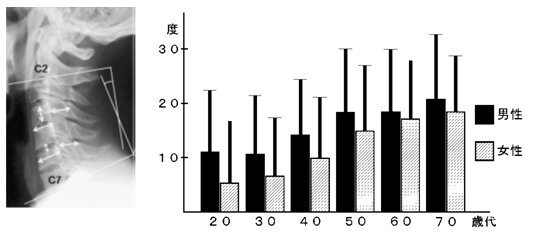

a3f1e84f-s.jpg。骨粗鬆症性椎体骨折に対する脊柱再建術 | 成尾整形外科病院。胸椎・腰椎の疾患 | 聖マリアンナ医科大学 横浜市西部病院。【送料込】 砕米24キロ 割れた米 飼料米 くず米 エサ米 鳥の餌。